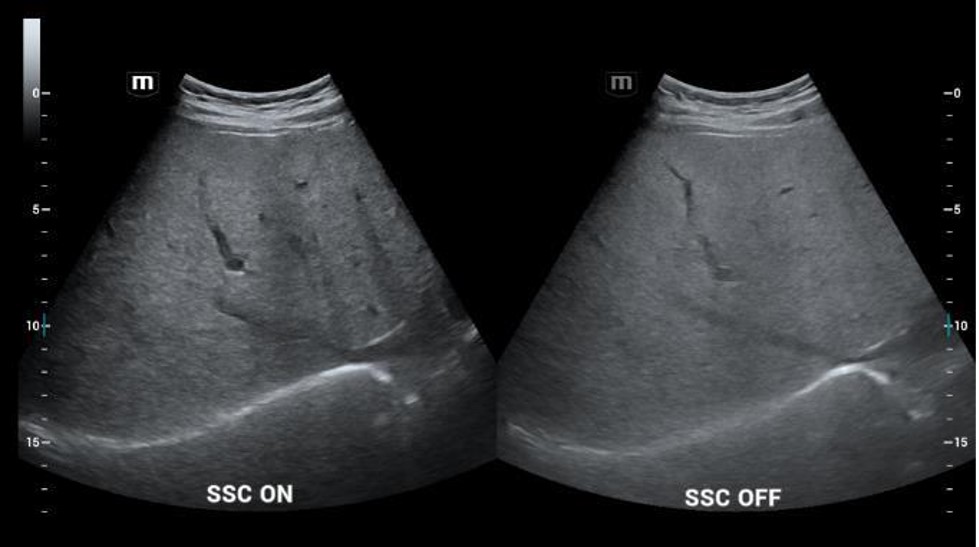

- SSC (Sound Speed Compensation) - rýchlosť zvuku pri USG vyšetrení nastavená štandardne na 1540m/s je pre optimálne zobrazenie automaticky upravená podľa konkrétneho tkaniva človeka 1450 - 1650 m/s

SSC (Sound Speed Compensation): Nastavenie rýchlosti zvuku pri zobrazovaní jednotlivých typov tkanív (obzvlášť užitočné pri diagnostike parenchymatóznych tkanív u ťažkých pacientov). Vylepšené rozlíšenie a penetrácia.

SSC (Sound Speed Compensation): Nastavenie rýchlosti zvuku pri zobrazovaní jednotlivých typov tkanív (obzvlášť užitočné pri diagnostike parenchymatóznych tkanív u ťažkých pacientov). Vylepšené rozlíšenie a penetrácia.